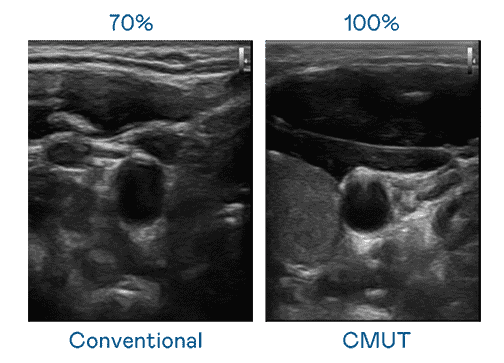

CMUT 技术是一种用电容式微机电元件来产生超音波讯号的技术。。。与传统 PZT 压电式技术相比,,,CMUT 频宽增加 30%,,更宽频的超音波讯号让影像解析度大幅提升,,是实现高影像品质医疗超音波扫描、、、促进精准医疗发展的关键技术。。。。

大频宽带来超清晰影像

超音波影像的解析度高低,,,首先取决于探头能发出的讯号频宽。。。。PA直营 CMUT 可提供高清晰的超音波讯号,,,,提供高频宽、、、、高灵敏度、、、影像纹理细节更高的超音波影像,,,,协助医护人员缩短影像判读时间及利用精准的医疗影像进行诊断。。。。